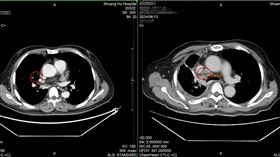

打完119就昏倒!他突胸痛竟主動脈剝離

別忽視胸痛警訊。65歲的劉先生,年前準備外出吃尾牙時...

2025/02/14 10:59